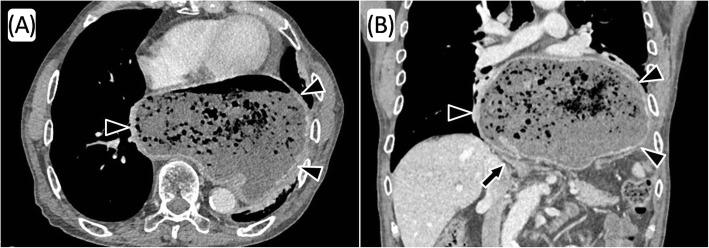

A 79-year-old man with a history of distal gastrectomy for submucosal benign tumor 40 years ago was referred to our hospital because of dysphagia and weight loss. Computed tomography revealed prolapse of the entire postoperative stomach into the mediastinum, and a radical operation was performed. There was a strong adhesion in the hernial sac of the mediastinum, but only little adhesion due to a previous open surgery in the abdominal cavity was present. After the stomach was pulled into the abdominal cavity, suture cruroplasty and Toupet fundoplication without dissection of the short gastric artery were performed. The patient experienced postoperative paralytic ileus, but the rest of the postoperative course was uneventful and the symptom of dysphagia improved.

一名79岁男性,40年前因黏膜下良性肿瘤行远端胃切除术,因吞咽困难和体重减轻转诊至我院。计算机断层扫描显示整个术后胃脱垂至纵隔,遂行根治性手术。纵隔疝囊内粘连严重,但因既往腹腔开放手术导致的腹腔内粘连较少。将胃拉回腹腔后,在不切断胃短动脉的情况下进行了缝合膈肌成形术和Toupet胃底折叠术。患者术后出现麻痹性肠梗阻,但术后其余过程顺利,吞咽困难症状改善。